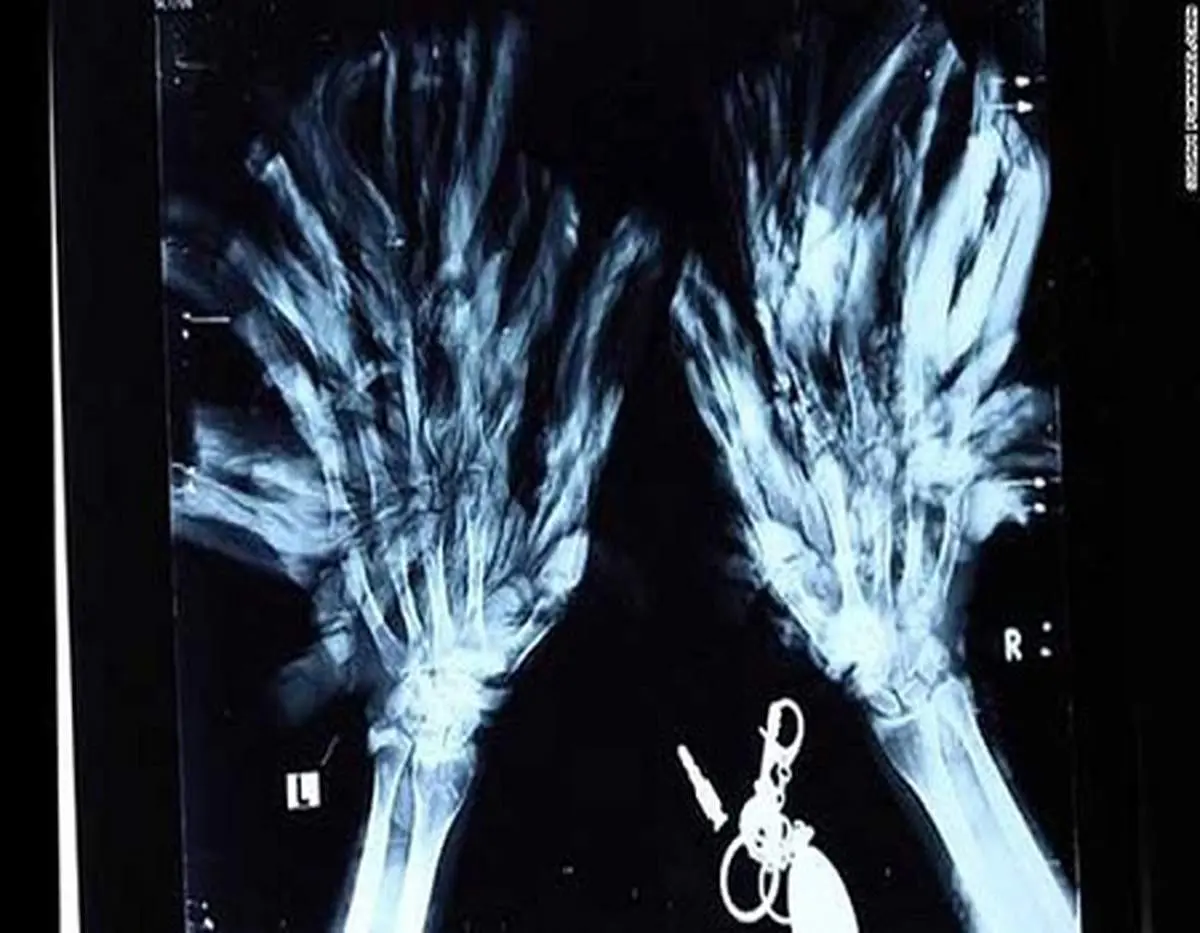

به گزارش منیبان؛ عبدالنصیر، شهروند ۳۵ ساله اهل شهر خاش در سیستان و بلوچستان دچار بیماری «اپیدرمودیسپلازی ورموسیفورم» یا بیماری «مرد درختی» شده است. بیماری نادری که فقط ۶۰۰ مورد ابتلا به آن در جهان ثبت شده است.

بیماری مرد درختی یا اپیدرمودیسپلازی وِروسیفورمیس نوعی بیماری ارثی نادر محسوب میشود. این بیماری که در اصطلاح عامیانه به آن بیماری درختی میگویند، موجب زائدههای پوستی زگیلمانند شبیه پوست درخت میشود و با خطر بالای ابتلا به سرطان پوست همراه است.

علائم اصلی بیماری مرد درختی رشد زائدههایی روی پوست است. این زائدهها بهطور کلی روی صورت، گردن، تنه، دستها و پاها ظاهر میشوند. آنها میتوانند تا عمق پوست گسترش پیدا کرده و در آنجا با اعمال فشار روی اعصاب موجب درد شوند.

زائدههای شاخمانند یا شبیه پوست و ریشه درخت که میتواند بسیار دردناک باشد

برخی از موارد سندرم مرد درختی شامل زائدههای پروتئینی بسیار بزرگ و سخت به نام کراتین میشود. کراتین همان مادهای است که شاخ، سم، پنجه و ناخن از آن تشکیل شده است.